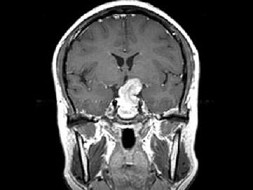

女,38岁,左侧视力下降伴头昏1个月余,根据所提供图像,最可能的诊断是()

A.颅咽管瘤

B.垂体嫌色细胞腺瘤

C.视神经胶质瘤

D.软骨瘤

E.脑膜瘤

[单选题]女,38岁,左侧视力下降伴头昏1个月余,根据所提供图像,最可能的诊断是()A . 颅咽管瘤B . 垂体嫌色细胞腺瘤C . 视神经胶质瘤D . 软骨瘤E . 脑膜瘤